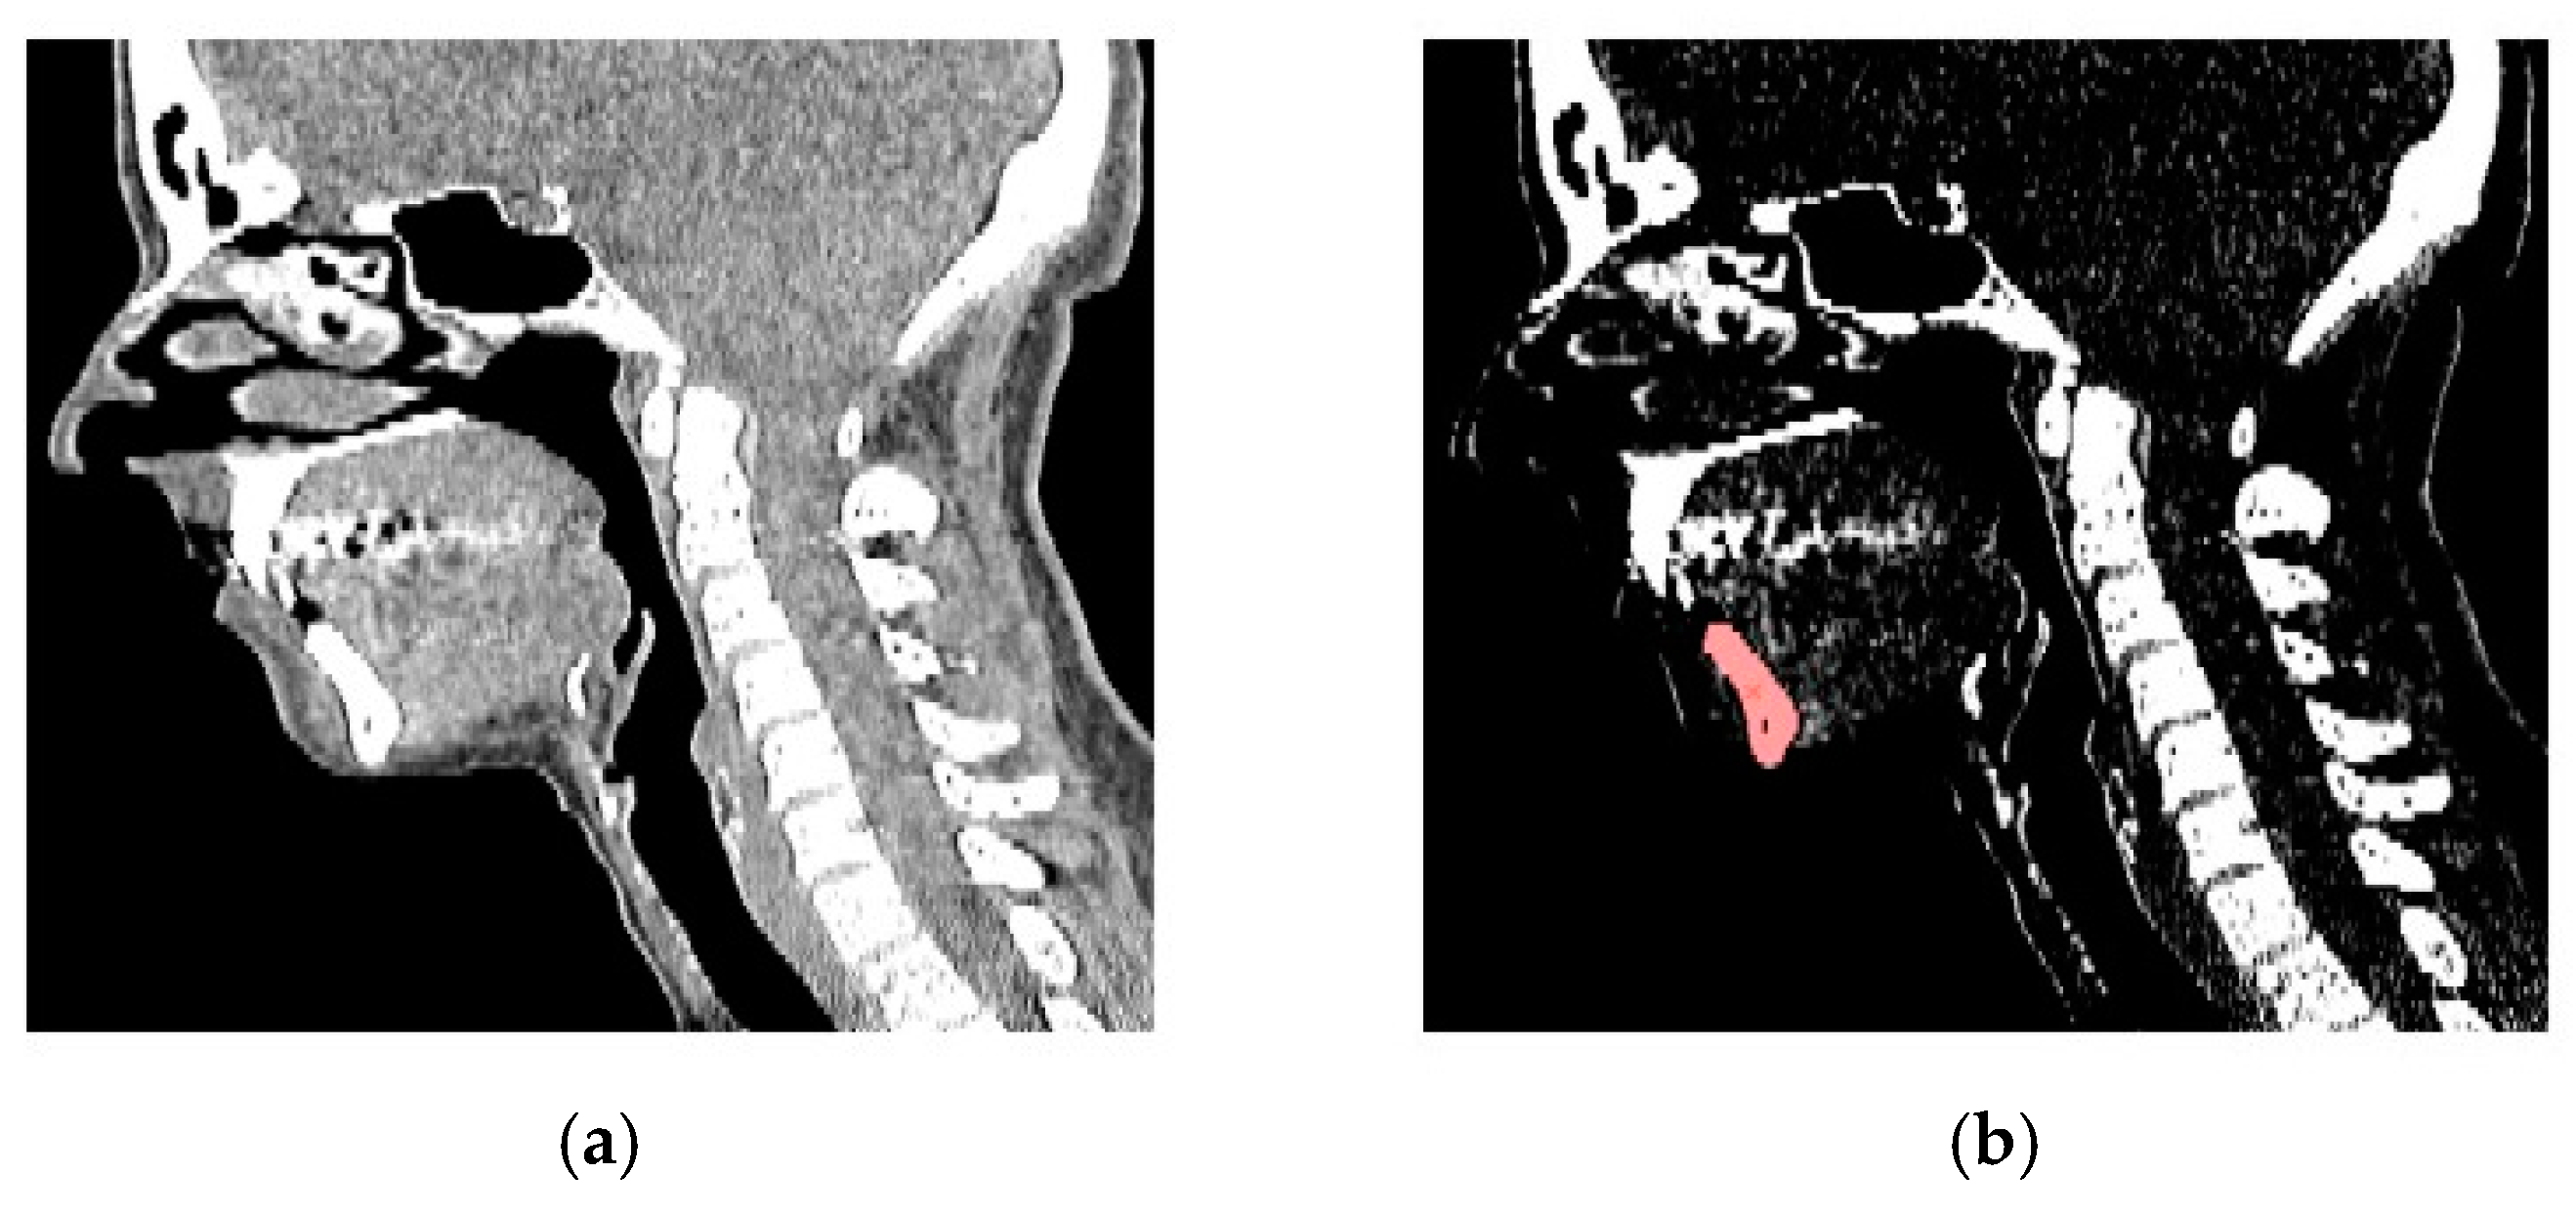

2.1. RE Modeling Process